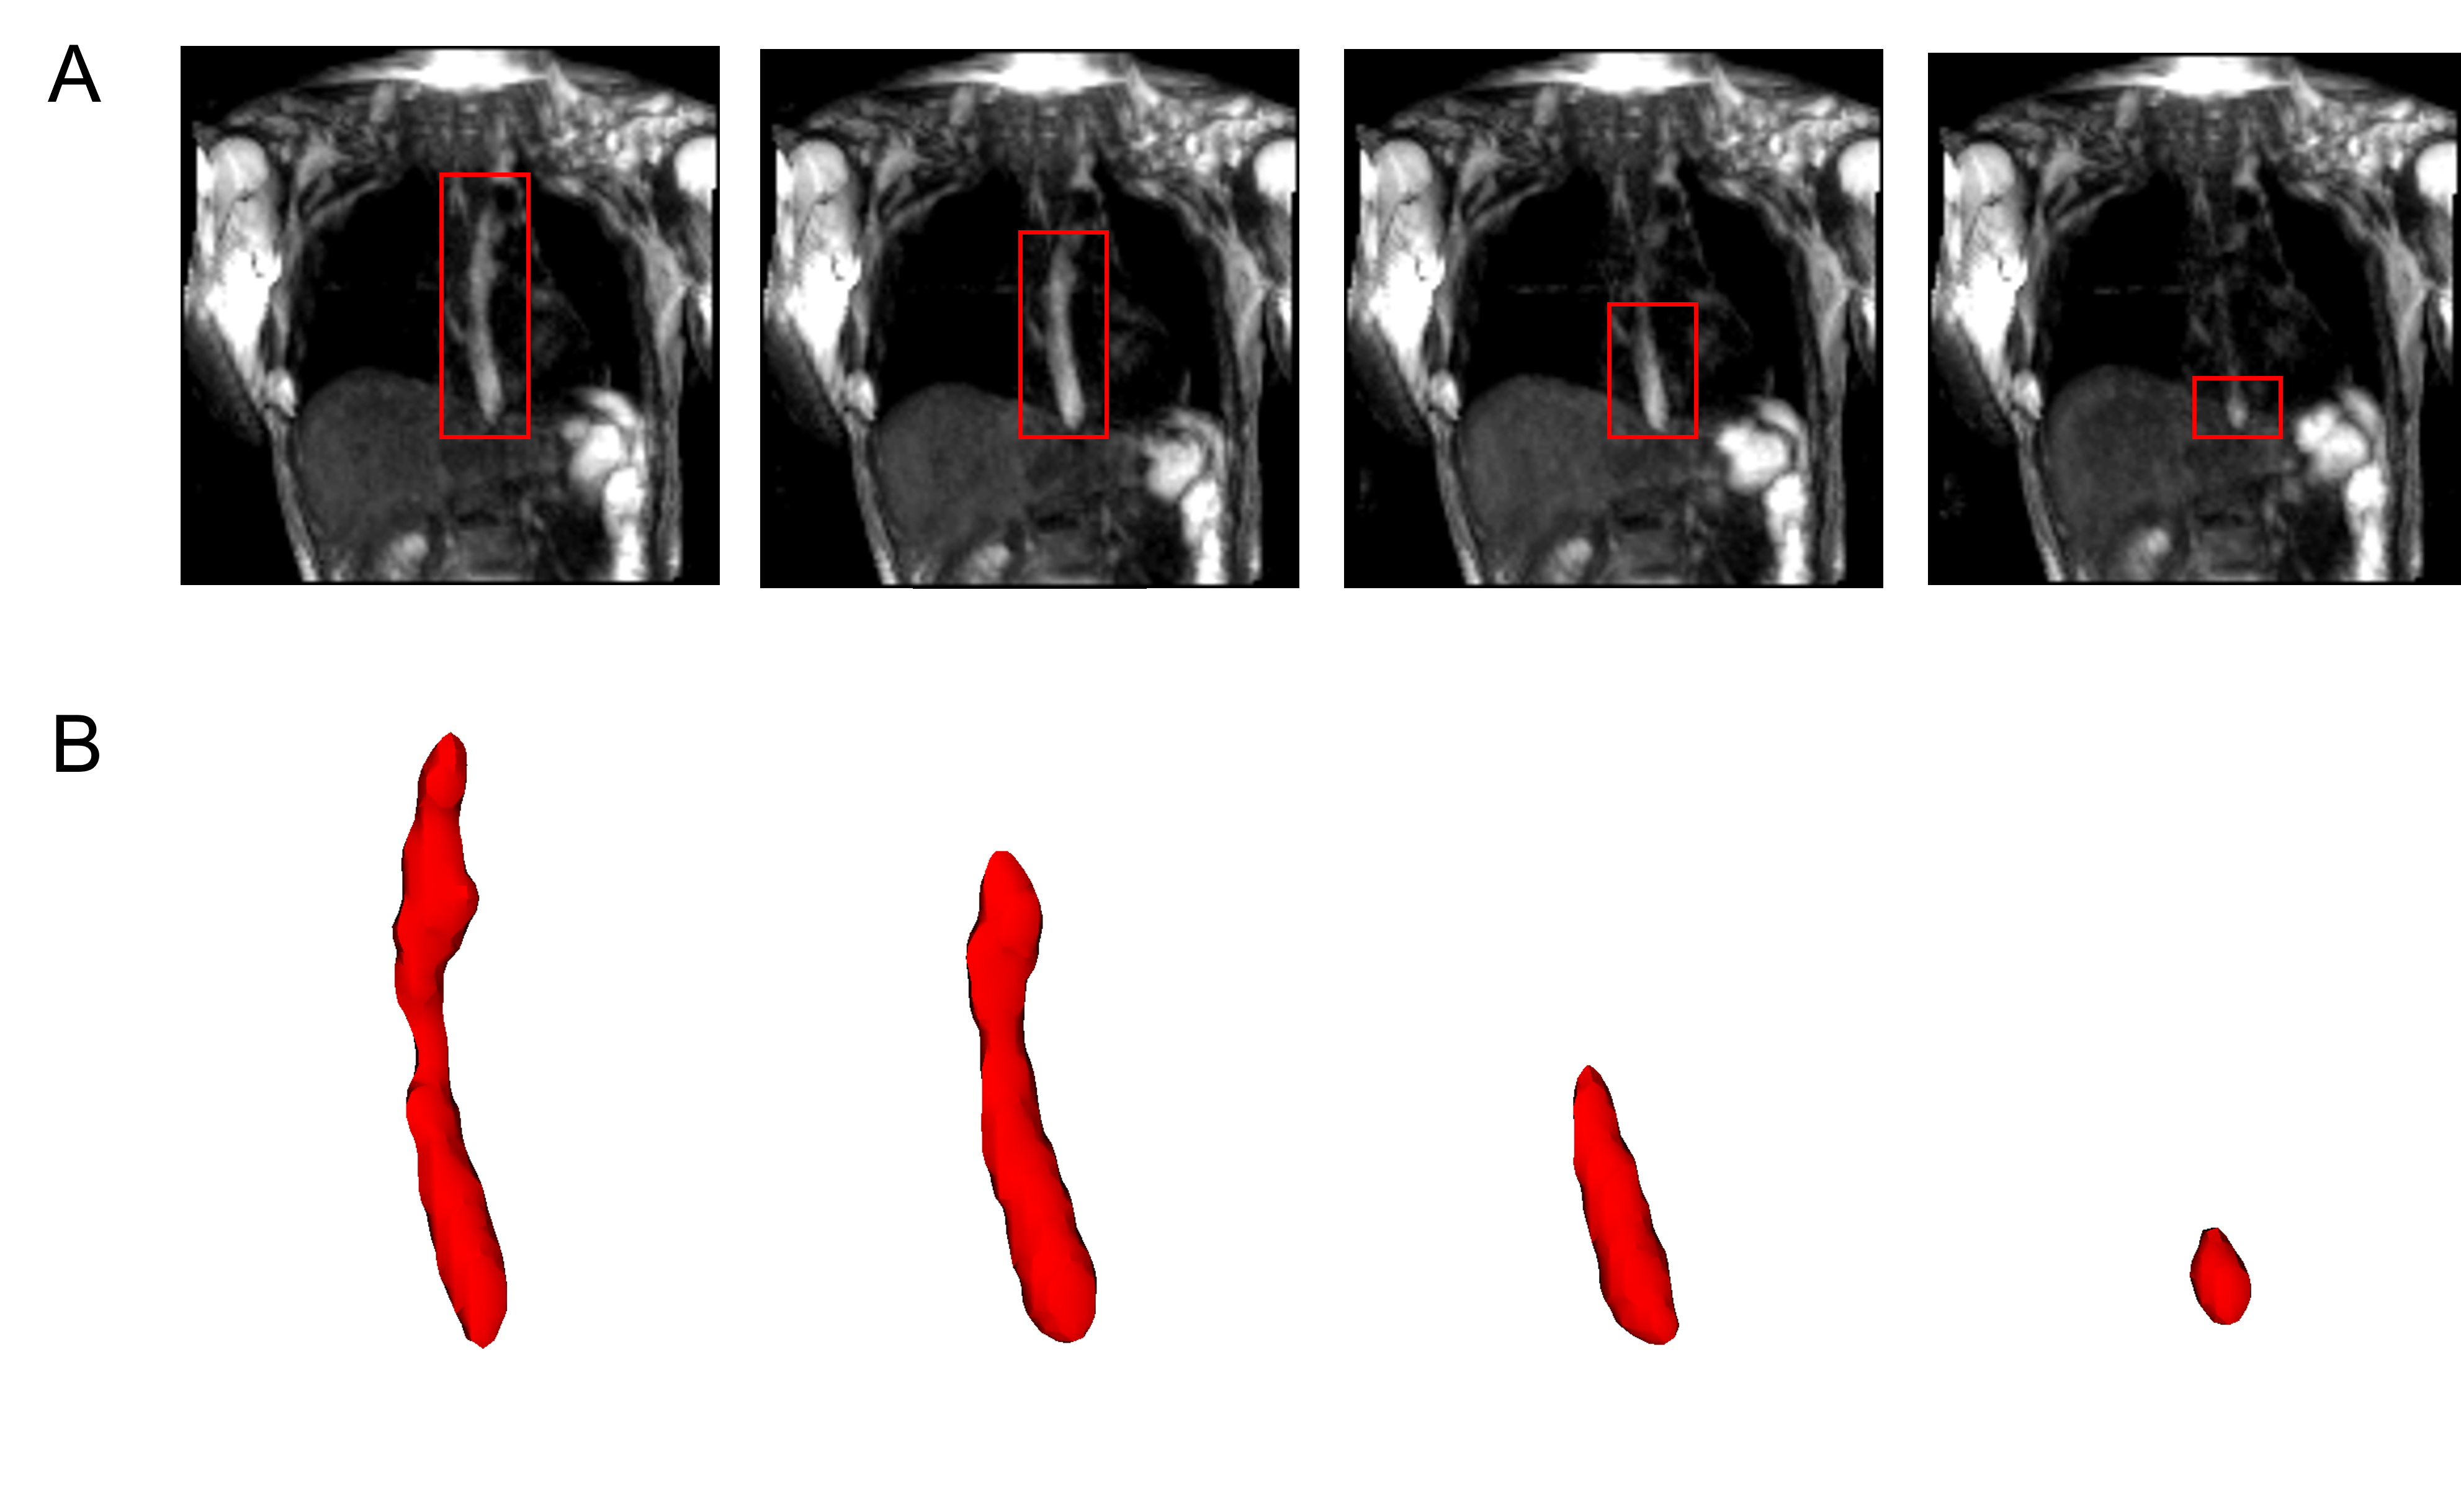

The MRI output consisted of a cuboid wherein voxels in a Cartesian coordinate system had different magnitudes of intensity. The temporal resolution of the dynamic MRI (1.17 second) determined the number of images with the bolus seen within the esophagus; 7 time instants in this study. The typical length of an adult esophagus is 18 - 25 cm [27]. The average velocity of a normal peristalsis is approximately 3.3 cm/s [28]. Thus, an average swallow sequence usually takes 5 - 8 seconds. Therefore, temporal resolutions similar to what we used in our analysis typically result in 5 - 8 images. Although this temporal resolution is not comparable to fluoroscopy, the detailed three-dimensional geometry of the bolus in MRI leads to better prediction of velocity and intrabolus pressure resulting in better prediction of esophageal wall properties. The bolus was manually segmented for the 7 time instants, a few of which are shown in Figure 2. The segmentation assigned a value of 1 and 0 to each voxel that lay inside and outside the bolus, respectively. The image segmentation was performed using the open-source software ITK-SNAP [29]. With improved MR imaging and better temporal resolution, manual image segmentation might not be feasible and more sophisticated automated segmentation techniques might be necessary. We have described a deep learning based automated segmentation approach called 3D-U-Net [30] in the Appendix which was fine-tuned for this application.

MRI-MECH modeled the esophagus as a one-dimensional flexible tube. For such one-dimensional analysis, the variation of cross-sectional areas at different points along the length of the esophagus and different time instants had to be extracted from the three-dimensional bolus obtained from segmentation. This was done in two steps. The first step was to generate a center line along the length of the esophagus. The bolus shapes observed at different time instants were superimposed and then cross-sections of the superimposed shape at different horizontal planes from the proximal to the distal end of the superimposed shape were generated. The centroids of these cross-sections were connected to form the center line. The length of the center line in this case was 9.65 cm. The second step, after extracting the center line, was to generate planes perpendicular to the centerline as shown in Figure 3. The segmented voxels marked 1 which lay near these perpendicular planes were projected onto these planes. These projected points were connected using Delaunay triangulation as shown in Figure 3. The cross-sectional area at each point along the center line was then calculated as the sum of the triangles in the Delaunay triangulated geometries.